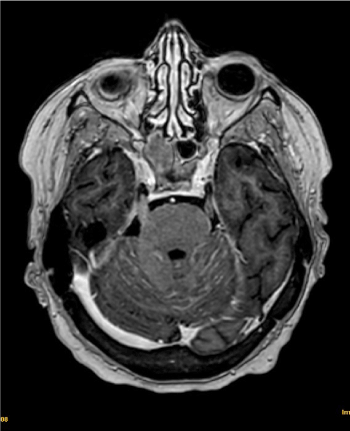

Given the persistence of the clinical picture, we decided to admit and repeat CT with contrast iv, which describes findings compatible with leptomeningeal involvement in posterior cranial fossa (Figure 1), these findings being subsequently confirmed by brain magnetic resonance imaging (MRI) (Figure 2).

Figure 2. Brain MRI findings: Linear contrast capture and signal alteration at the level of the fourth ventricle and multiple cerebellar folia

Another tool that can support the diagnosis in the presence of a negative CSF cytology is brain MRI with contrast. Using this imaging technique we can observe diffuse meningeal enhancement with nodular deposits in the meninges [5,6].

In the face of clinical suspicion and given that the sensitivity of the cytology is limited, imaging has become the initial, and often the only, diagnostic tool with sensitivity between 76-87% [4,6].